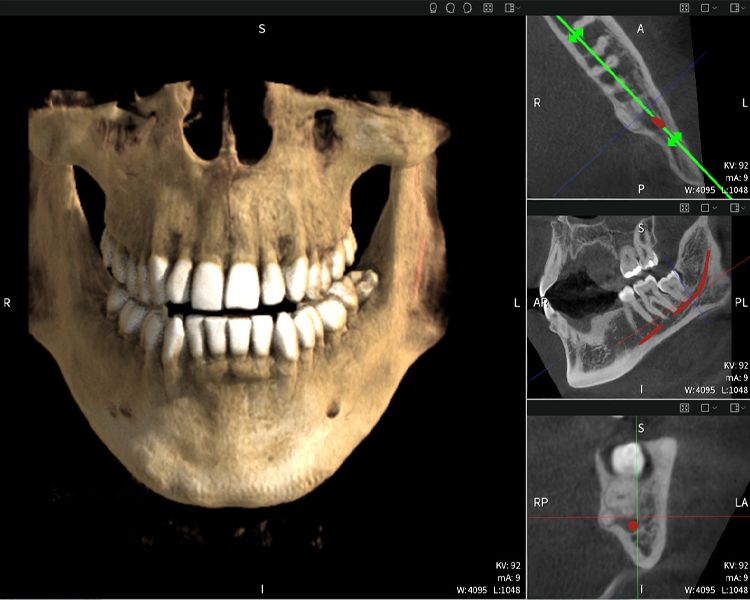

Figure b: Imaging results of Seethrough Max, in front of a black background.

Figure b

Figures b–d show various views of a 3D reconstruction of the mandible, providing a comprehensive overview of the mandibular anatomy, the position of the nerves in relation to the teeth, and allowing assessment of tooth symmetry and alignment.